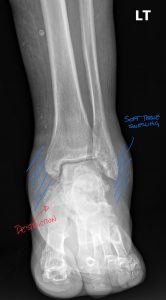

Radiographs are the workhorse for established Charcot. The classic findings are known as the “6 D’s”.

Interpreting these findings can be complex, especially in the early stages. The initial radiology report may be deceptively nonspecific, mentioning only “severe degenerative changes” or “comminuted fracture” without synthesizing these findings into the primary diagnosis of neuroarthropathy.

This is where Expert radiology consultation is critical. If the clinical picture suggests Charcot but the initial imaging is equivocal or the report is non-committal, do not hesitate to seek a Second opinion report. Specialist diagnostic imaging consultants—such as a musculoskeletal radiologist or a DACBR (Diplomate of the American Chiropractic Board of Radiology)—are trained to spot the subtle, early signs of neuropathic destruction.